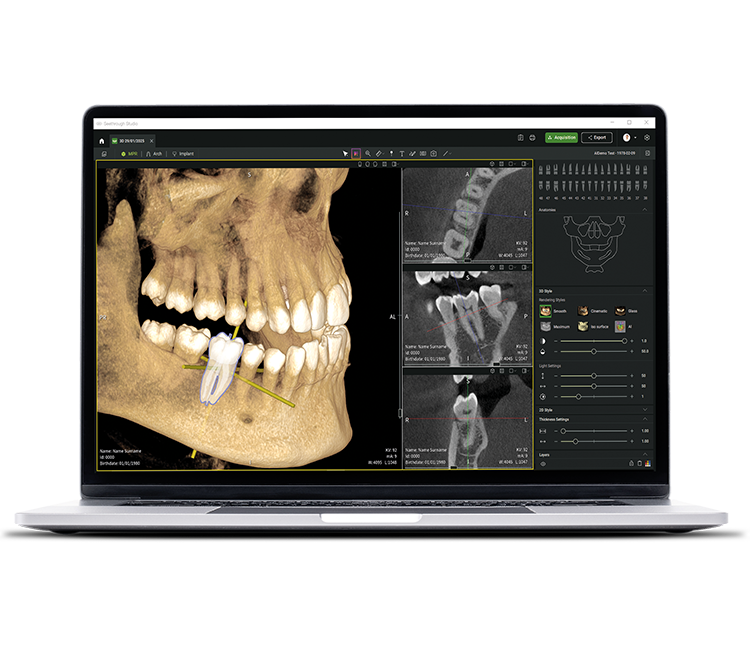

Además de las sofisticadas tecnologías de hardware, el revolucionario software Seethrough Studio es el factor decisivo para el alto nivel de toda la gama de productos radiológicos de W&H. Con funciones útiles y algoritmos avanzados, Seethrough Studio es una solución completa que lleva los flujos de trabajo digitales y de radiología en odontología a un nuevo nivel.

Herramienta de planificación de implantes integrada

Además de la excelente calidad de imagen y el uso intuitivo, Seethrough Studio ofrece numerosas funciones útiles, como la herramienta de planificación de implantes integrada de serie para facilitar la visualización y la preparación del tratamiento.

Funciones asistidas por IA